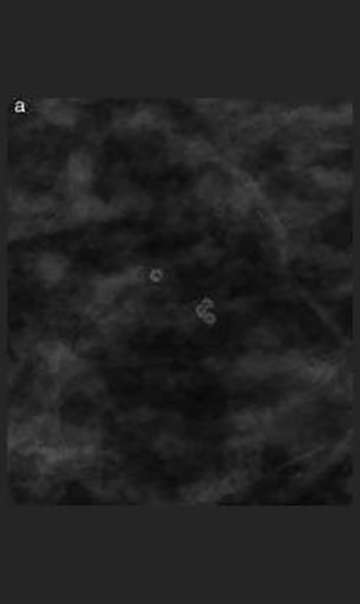

Milk of calcium calcifications

Milk of Calcium Calcifications: Craniocaudal View